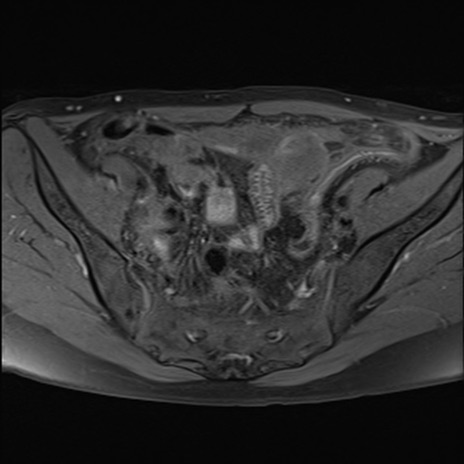

症例39 脂肪抑制T1WI(横断像)

MRI(4日後)

T1WI(横断像)